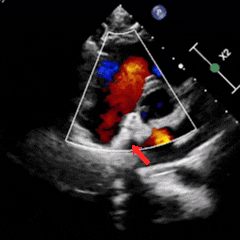

释放后多切面下观察,封堵器位置正确、形态良好、夹持稳定,封堵手术成功

术后1周复查心脏彩超提示可降解封堵器形态位置良好,无残余分流,周围其他结构无异常。

术后1月随访,患者自述症状较前明显减轻,复查心脏彩超提示可降解封堵器形态位置良好,无残余分流,周围其他结构无异常。